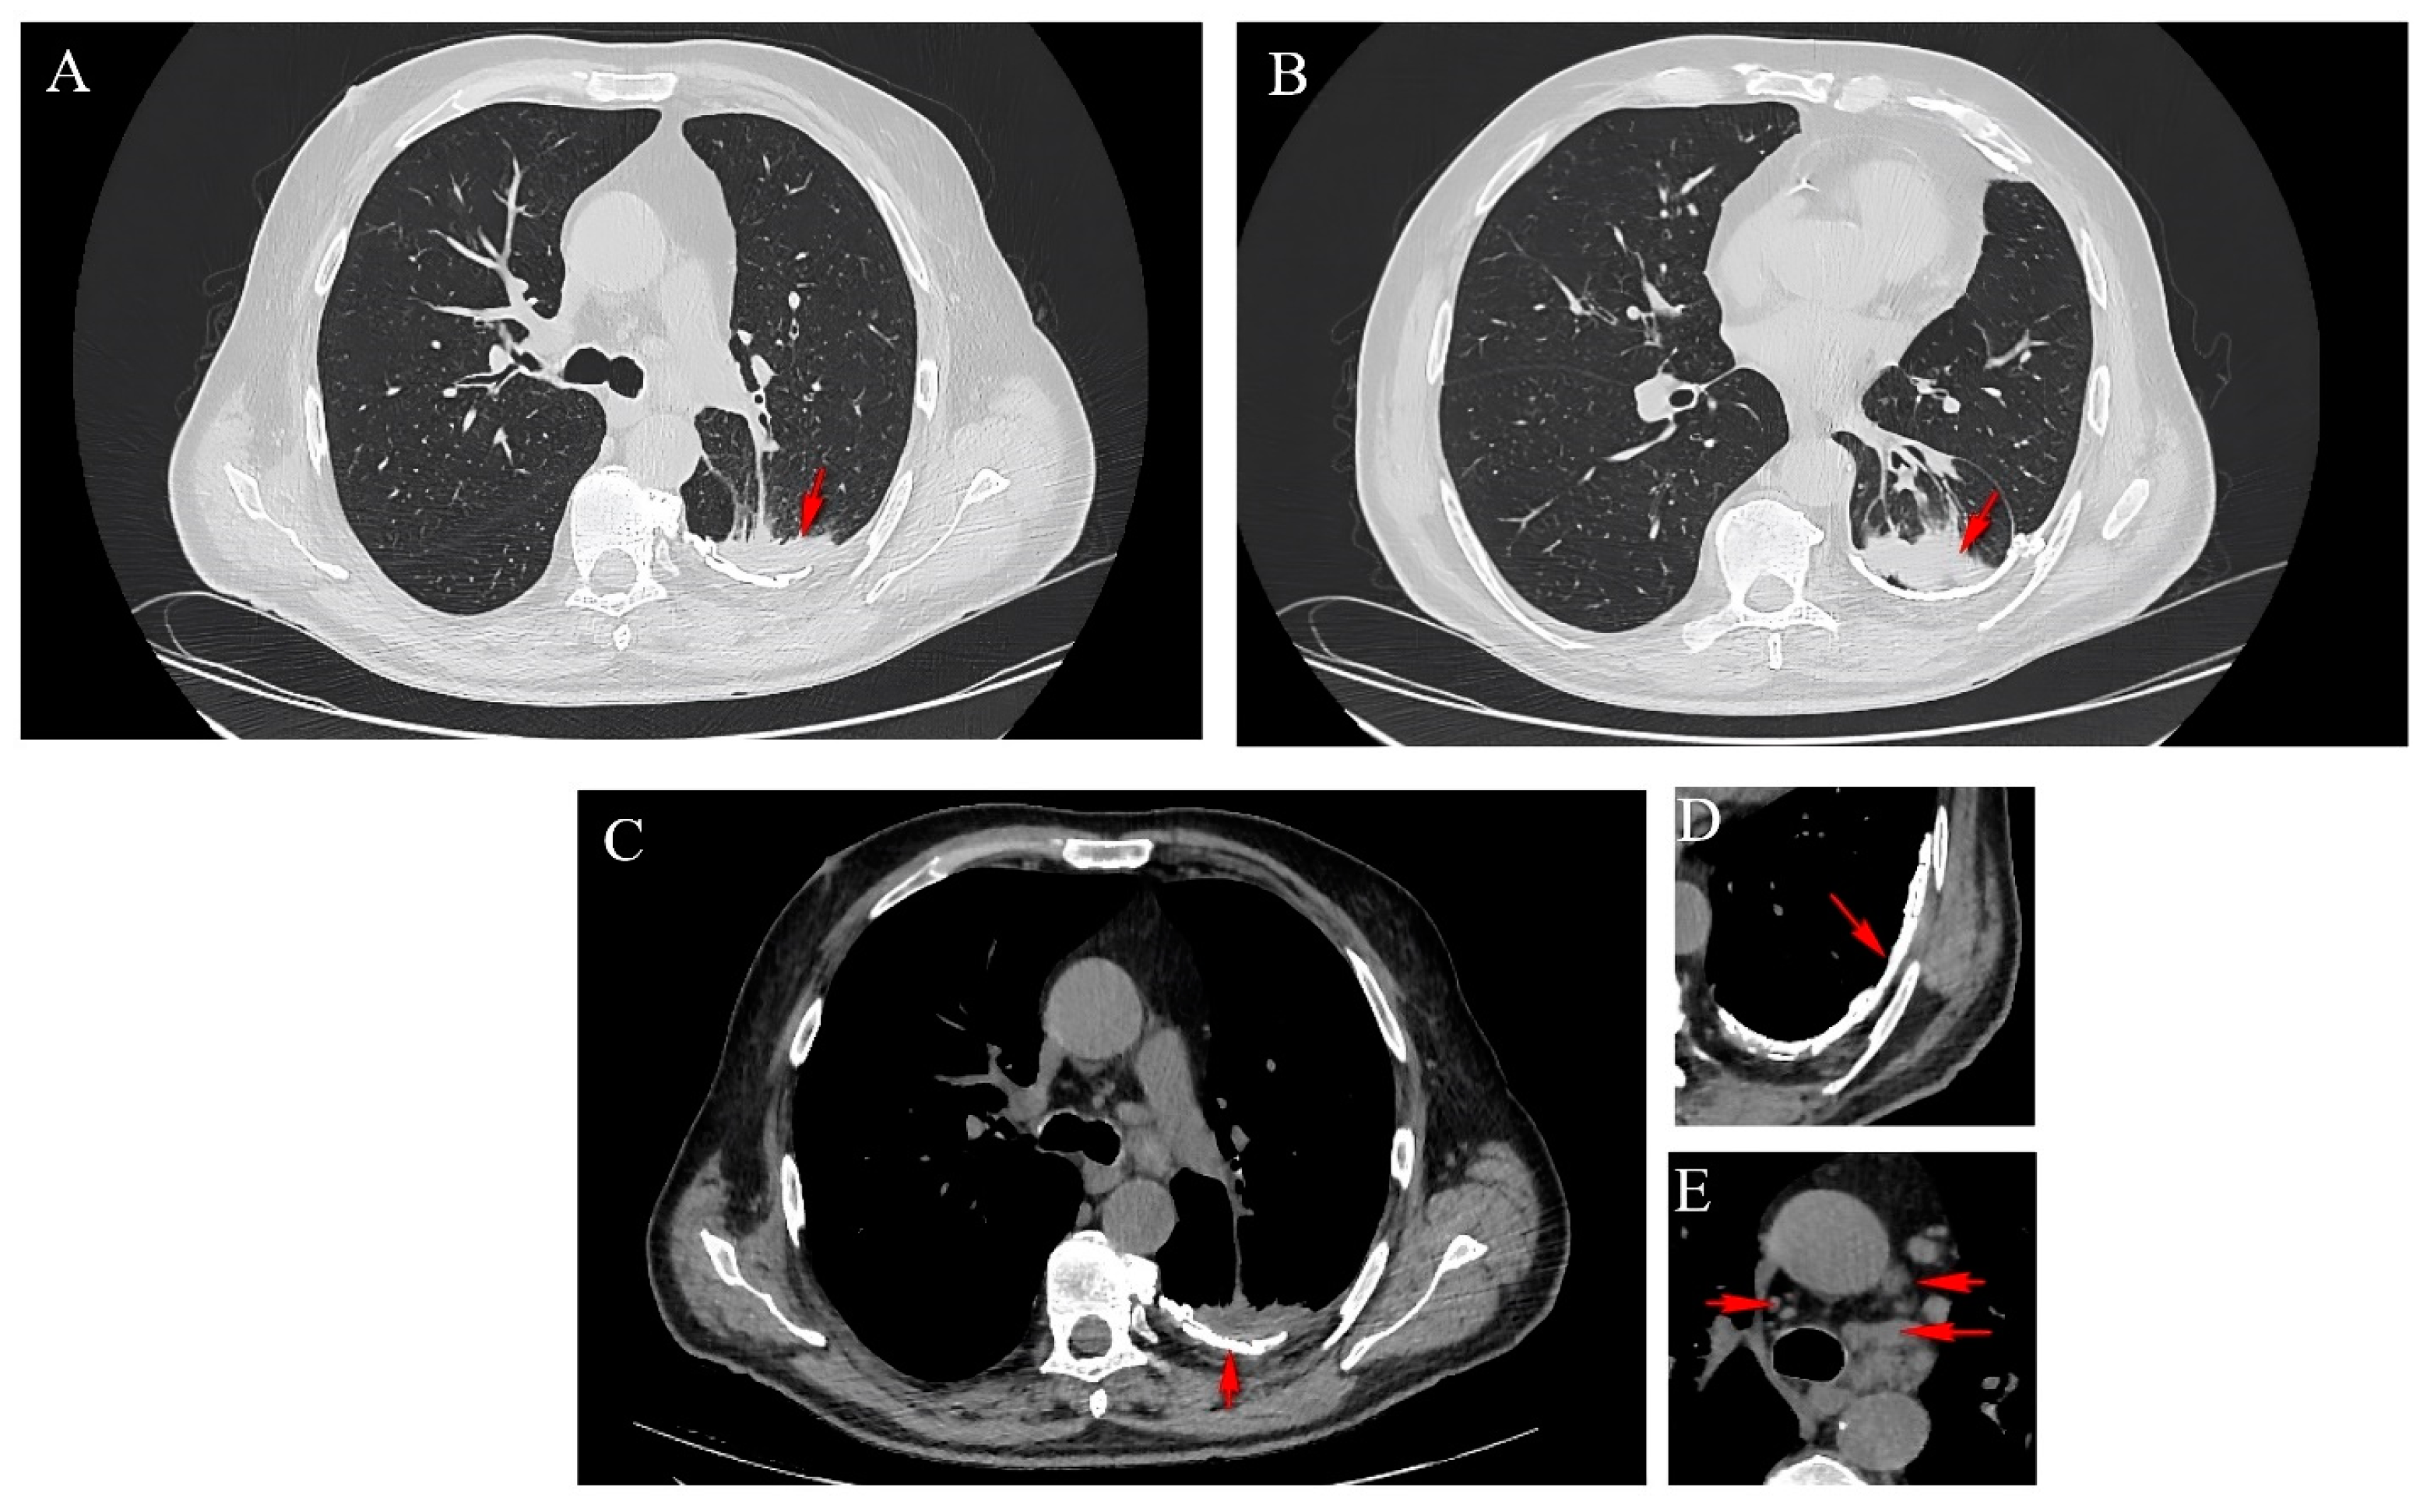

2.2. Thoracic Computed Tomography